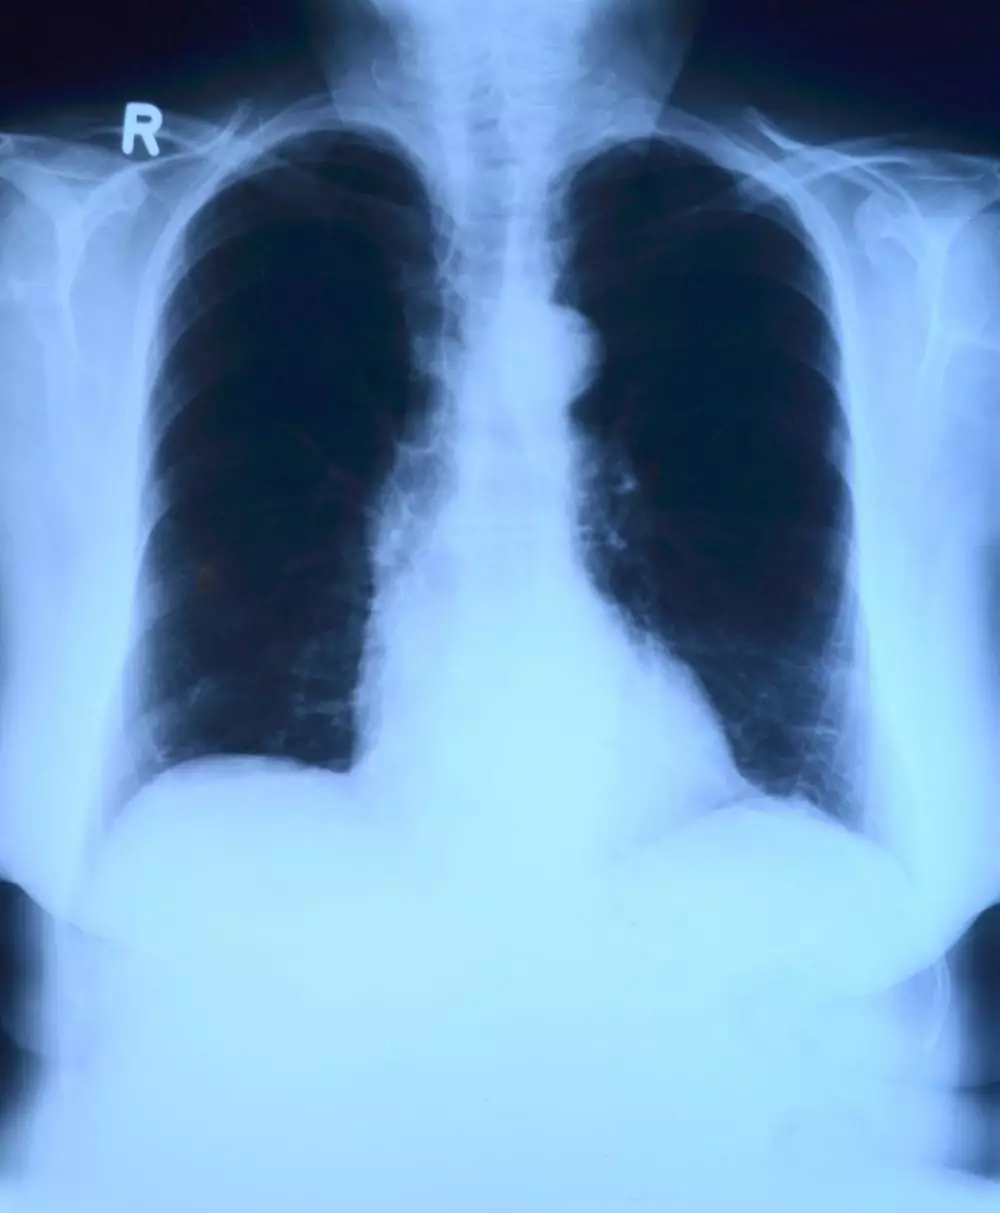

Ketika udara terakumulasi di ruang pleura, tekanan yang dihasilkan dapat menyebabkan paru-paru kolaps, kondisi yang dikenal sebagai pneumotoraks. Gejala yang umum terjadi meliputi nyeri dada mendadak yang tajam, terutama saat bernapas dalam-dalam atau batuk, sesak napas, dan dalam kasus yang parah, penurunan tekanan darah serta sianosis (kulit kebiruan akibat kekurangan oksigen). Diagnosis pneumotoraks biasanya dilakukan melalui pemeriksaan fisik dan konfirmasi dengan pencitraan medis seperti sinar-X atau CT scan.

Gejala kanker paru-paru bisa termasuk batuk kronis, nyeri dada, penurunan berat badan tanpa sebab jelas, dan sesak napas. Diagnosis biasanya melibatkan pencitraan medis seperti sinar-X dan CT scan, serta biopsi untuk mengkonfirmasi keberadaan sel-sel kanker. Pengobatan tergantung pada stadium kanker dan dapat mencakup pembedahan, kemoterapi, radiasi, dan terapi target. Pencegahan terbaik adalah menghindari penggunaan produk vaping dan paparan zat-zat karsinogenik yang terkandung di dalamnya.